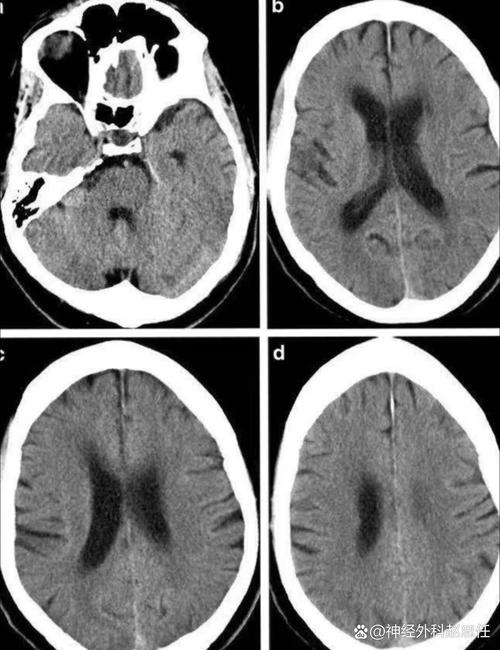

| 检查方法 | 出现异常的时间 | 对脑梗死的诊断价值 |

|---|---|---|

| 头部CT平扫 | 发病后6小时以上 | 发病6小时内通常完全正常,容易漏诊。 |

| 常规MRI (T1, T2像) | 发病后4-6小时 | 比CT稍早,但在“黄金时间窗”(4.5小时内)内可能仍不明显。 |

| DWI (弥散加权像) | 发病后数分钟至1小时 | 一旦发现高信号,基本可以确诊为急性脑梗死。 |